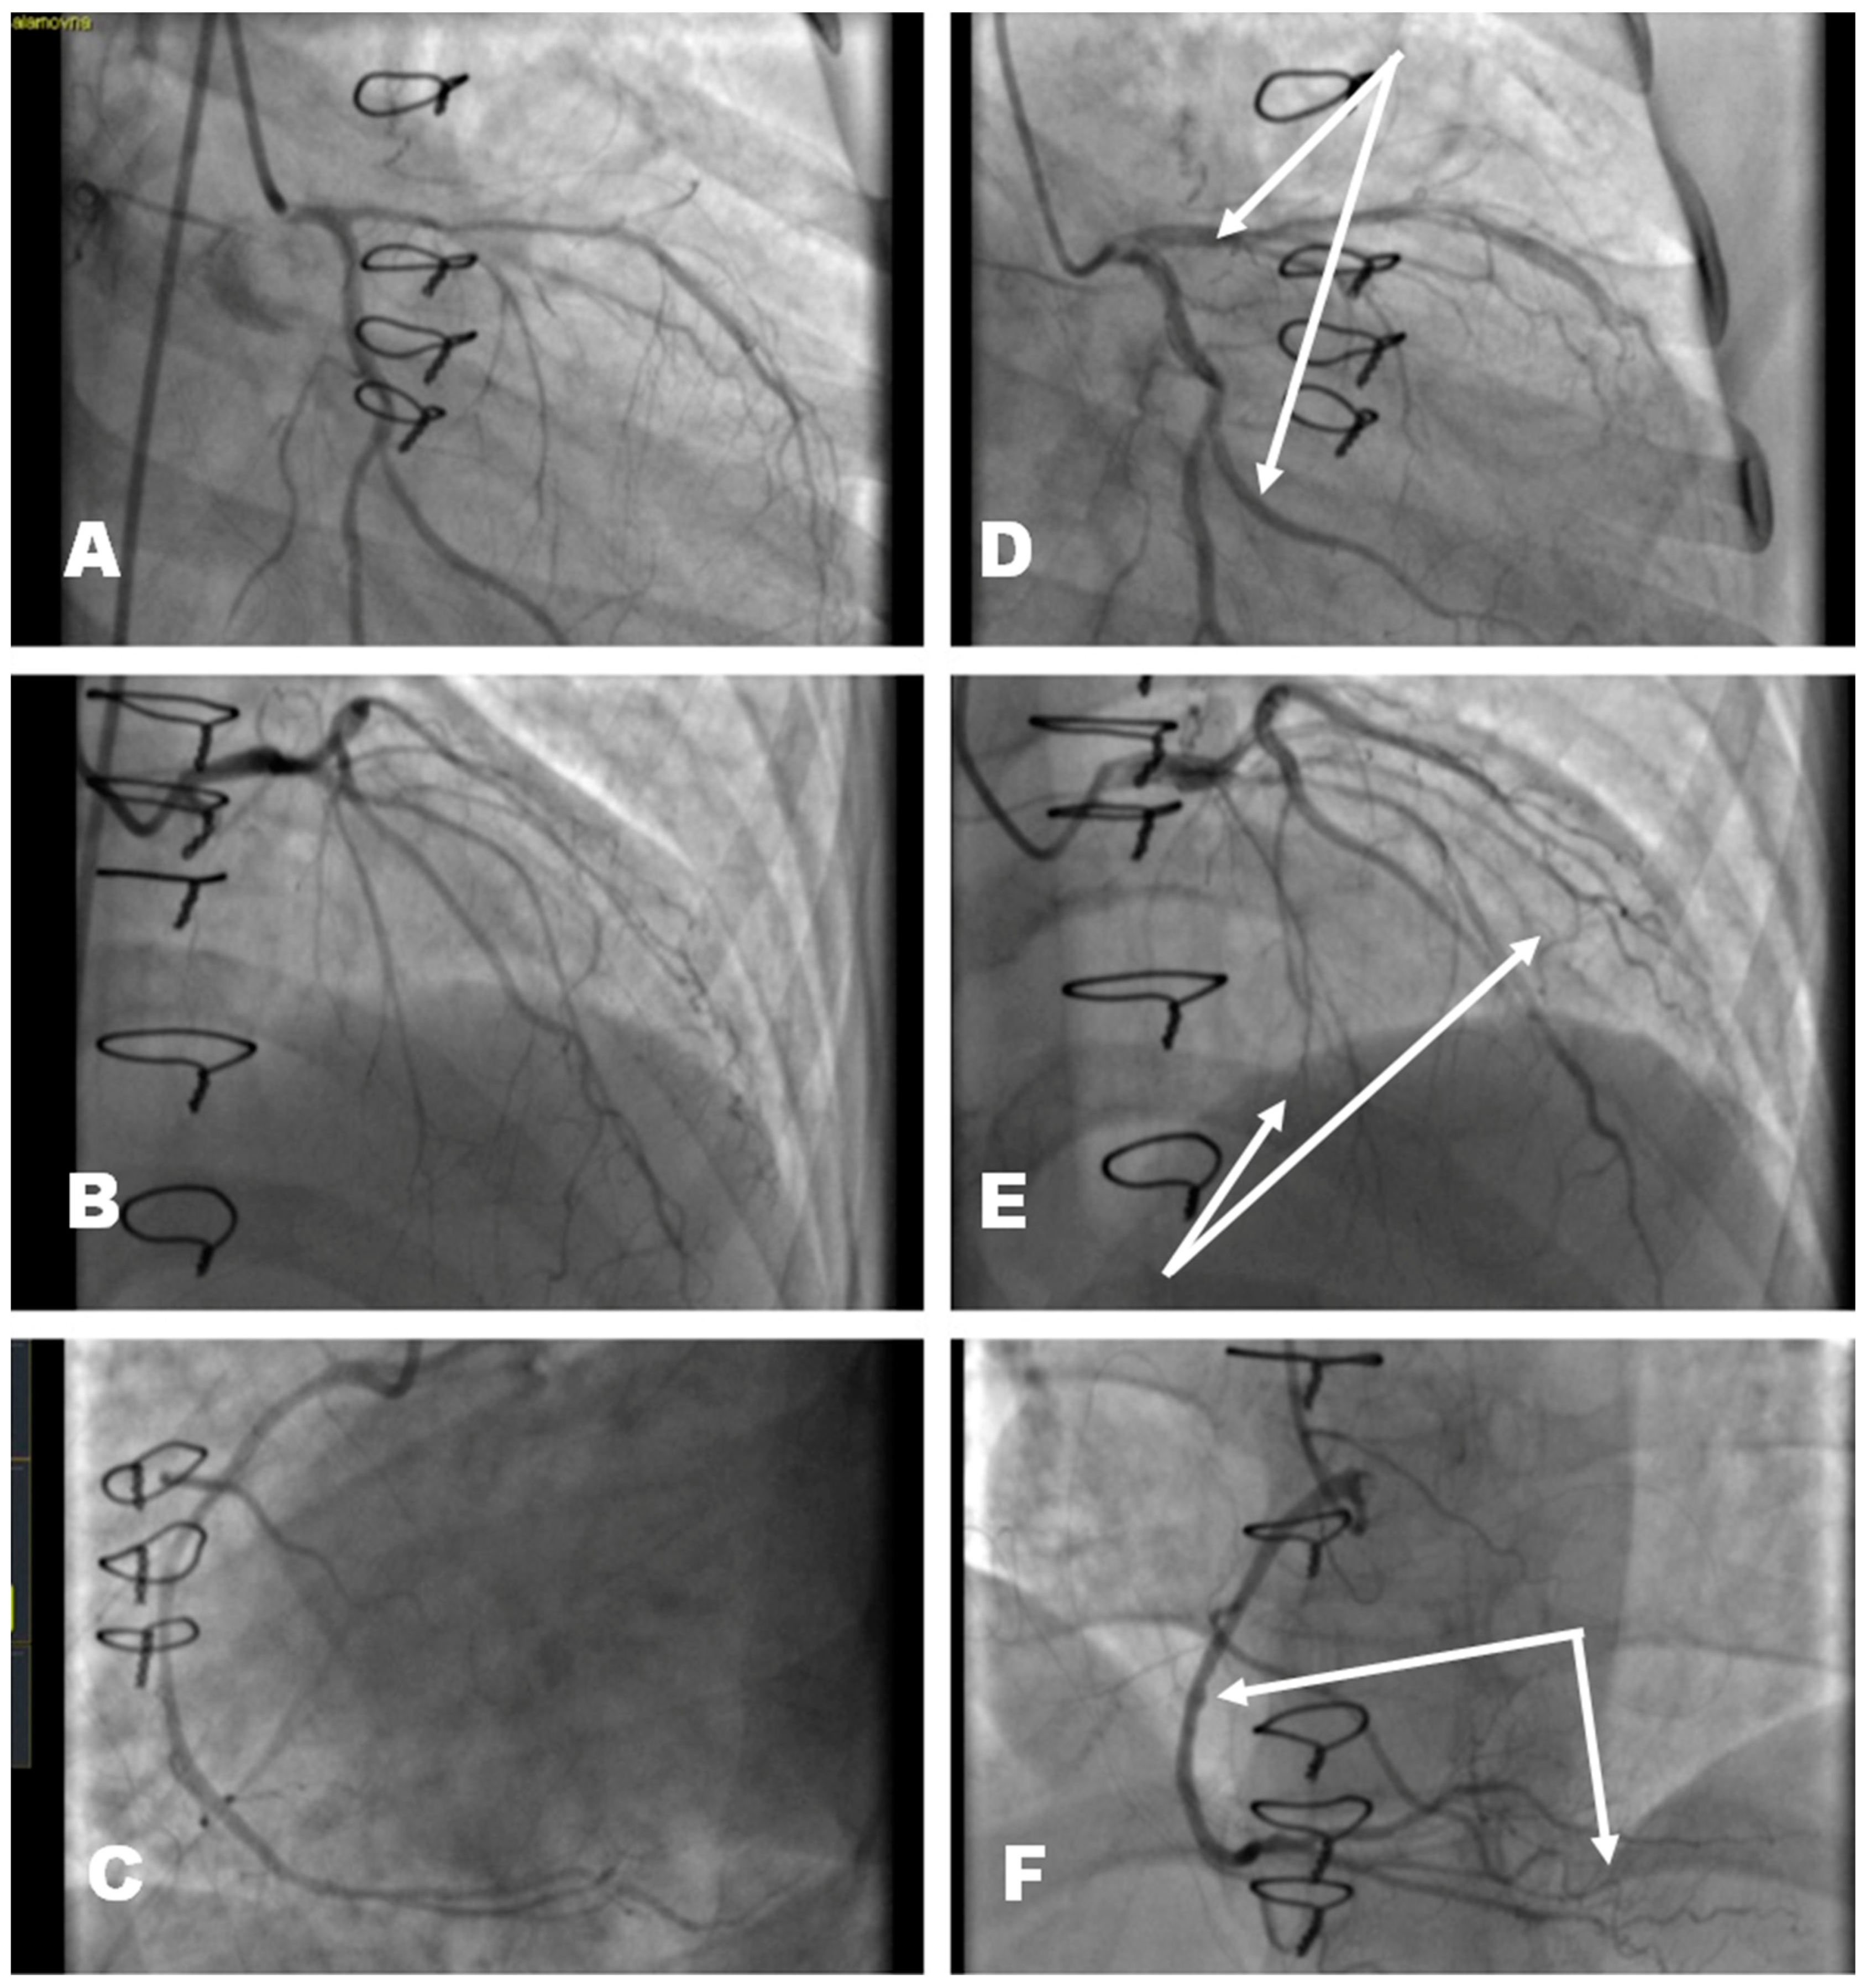

According to the results of the thoracic X-ray (Figure 1) and chest computed tomography (CT), there were signs of interstitial changes in both lungs; however, no infiltrates—such as hydrostatic edema, seen predominantly in the basal sections—were found. There were no data for pulmonary thromboembolism of the pulmonary artery and its branches, as well as infiltrative changes. The lung fields were without infiltrative changes. Hypoventilation of the basal sections. Interstitial enhancement of the pulmonary pattern.

Figure 1. Thoracic X-ray results upon admission of a patient with signs of severe congestion.